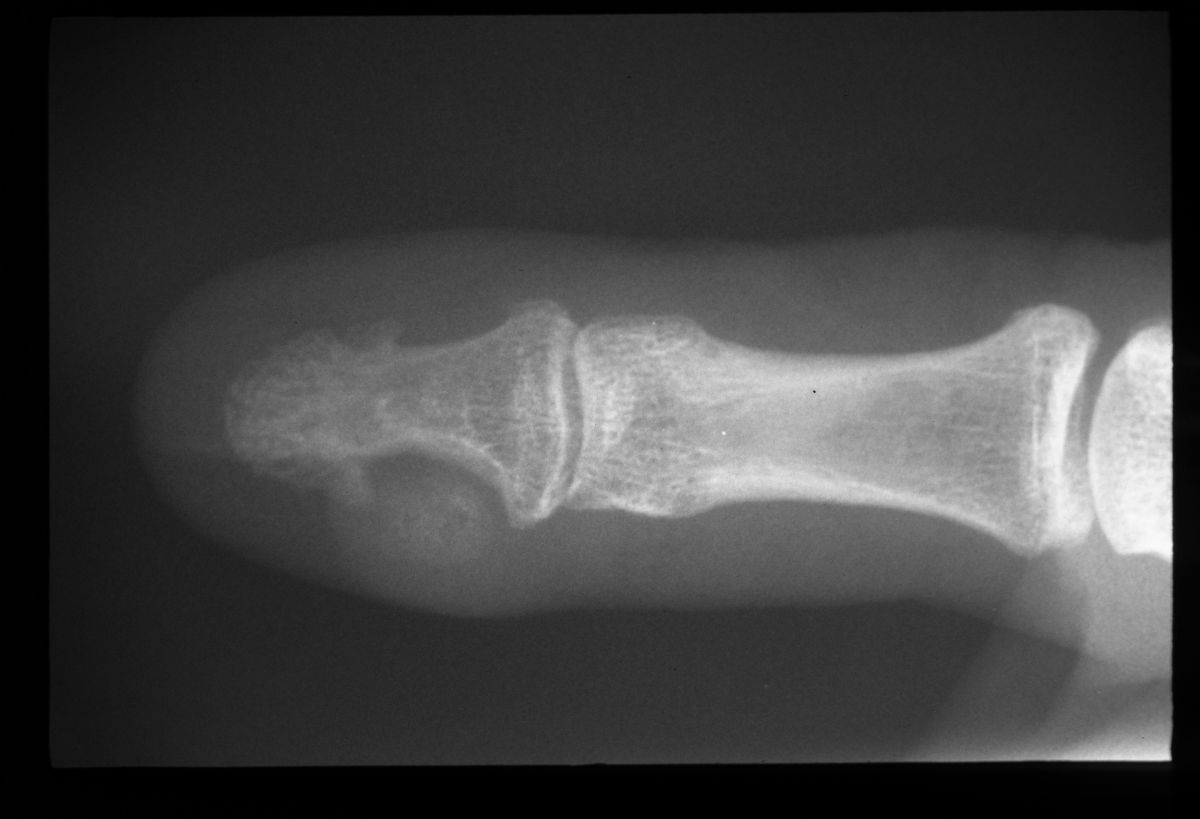

Nail deformity from subungual bone tumor. This patient has multiple hereditary exostoses.

Highslide